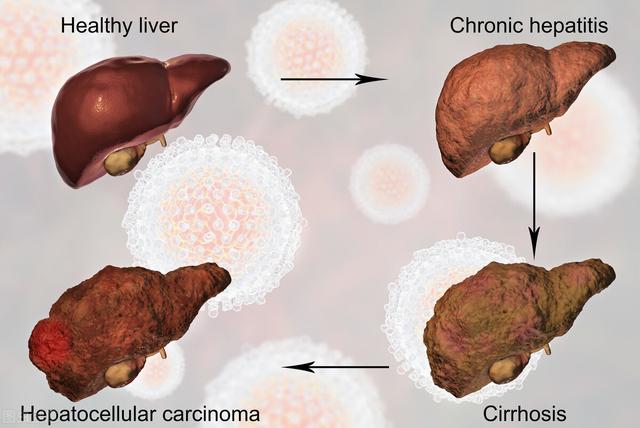

4、肝臓癌は、AFPと肝臓超音波検査のための採血を恐れている。

B型肝炎、C型肝炎、肝硬変、肝がんの家族歴、その他の自己免疫性肝疾患のある患者では、6ヵ月ごとにAFP(アルファフェトプロテイン)の血液検査と腹部超音波検査を行うことが推奨される。

(5)肝癌

大量の飲酒を長期間続けている人、慢性B型肝炎患者、肝硬変患者、化学物質を扱う仕事を長期間続けている人は、年に1回、肝機能検査を受けることを勧められる。エコー検査必要であれば、以下を実施する。肝拡大CT検査。

腫瘍マーカーAFP(α-フェトプロテイン)。

(4)慢性アルコール中毒、夜更かし、肝炎患者、B型肝炎キャリア。年に一度は検査を。

スクリーニングの焦点:肝臓がん

経験:超音波検査とα-フェト蛋白スクリーニング。